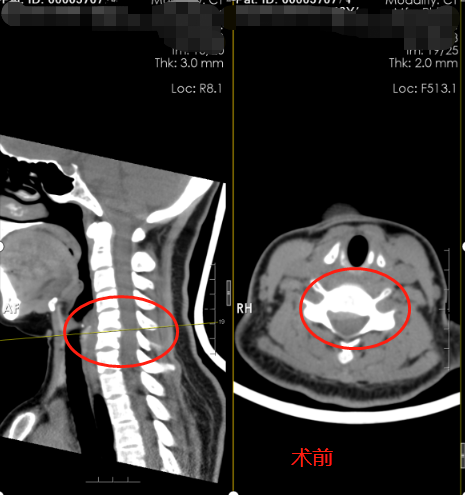

4月28日彭阿姨便马不停蹄踏上了南下广州的路。29日顺利入住的广东三九脑科医院神经外十科。主管医生热情的接待了她,详细询问病史后完善了相关的检查。医生解释,彭阿姨的颈椎病是属于神经根型颈椎病,是颈椎退变引起神经根的病变,主要表现为颈肩部疼痛、手臂和手指的麻木和无力,大部分经过颈椎牵引、针灸等物理治疗即可,像彭阿姨的这种经过保守治疗不能缓解的,可行手术治疗。手术需沿着颈部自然的纹理做3cm的切口,术后疤痕能最小化,显微镜下精细化的操作做到神经根充分减压,全程的神经电生理监测预警系统可以为手术保驾护航,出现瘫痪的概率极低。很快,神经外十科团队为彭阿姨制定了缜密的手术方案。4月30日,医生为彭阿姨进行了颈前路C5-6椎间盘切除减压融合术+神经根减压术。术后第一天彭阿姨惊喜的发现右手麻木消失,右手也可以抬起来了。彭阿姨的丈夫高兴的说,终于可以看见阿姨有笑容了。术后第五天,满心欢喜的出院回到湖南老家。